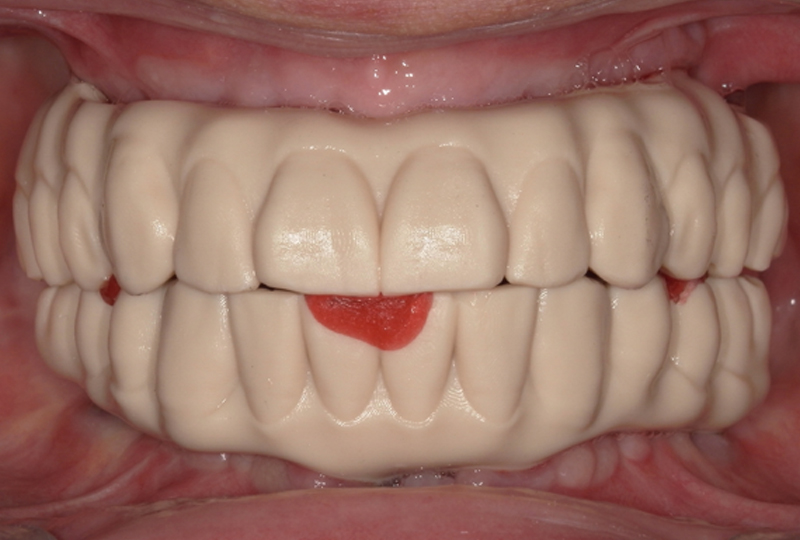

La proposta protesica fu una riabilitazione fissa supportata da impianti sia per l’arcata superiore che per quella inferiore, attraverso tecnica All-on 4. Prima della fase chirurgica, in un unico appuntamento, venivano acquisite le foto extra-orali in posizione di riposo, con un sorriso appena accennato, il massimo sorriso possibile, la CBCT delle arcate (ProMax 3D® Planmeca), le scansioni orali (TRIOS® 3, 3Shape) e le scansioni facciali (POP-2®, Revopoint) con un repere di posizionamento, in posizione di riposo e massimo sorriso. Con queste informazioni era possibile procedere, attraverso due sessioni di chirurgia eseguite secondo la tecnica All-on-4, al posizionamento di due protesi fisse a carico immediato in PMMA (Ceramill A-temp®, Amann Girrbach) (Figure 3,4).

Durante la visita successiva a quella delle impronte (secondo appuntamento) veniva effettuata la prova estetica utilizzando dei prototipi delle protesi definitive. Infatti i progetti venivano stampati in 3D in resina (Dental-try®, Asiga) e provati per verifiche di congruità e approvazione del paziente (Figura 14). In questa stessa fase si validavano le mesh per ottenere delle basi di lavoro virtuali corrette. Il Ringfix® era collocato in bocca e fissato mediante resina fotopolimerizzabile a dei particolari scanbody chiamati Scantransfer (Scantransfer®, IPD) (Figura 15).